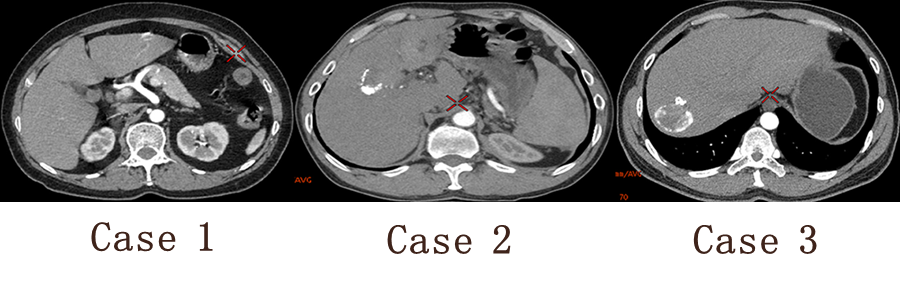

能谱CT诊断: Case 1 血管瘤 Case 2 肝癌介入术后碘油沉积 Case 3 肝包囊虫

Case 1 GSI 基物质图像定性分析

肝左叶实质性占位性病变,考虑血管瘤 Case 2 GSI 基物质图像定性分析

肝右叶高密度影 强化?钙化?

Case 3 GSI 基物质图像定性分析

肝右叶环形高密度影 强化?钙化?

病例点评及临床价值: 常规CT增强扫描,病灶有无强化直接影响病变的定性诊断,然而血肿、钙化在CT图像上亦呈高密度影,难以辨别,往往需要多期扫描,甚至追加平扫来加以鉴别、区分,增加患者辐射剂量。

能谱CT扫描能够获得各种基物质图像,在一期扫描中对病灶强化、血肿、钙化加以区分,满足病变定性需求,同时降低患者辐射剂量。